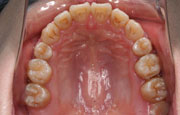

矯正の症例

| 【Before】 | 【After】 | |